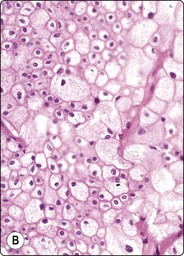

Most cortical adenomas subjected to FNB are asymptomatic lesions detected by abdominal CT in the preoperative investigation of patients with potentially resectable lung tumors, or incidentally by abdominal CT for other reasons (‘incidentaloma’). The main purpose of FNB is to exclude metastatic cancer. Smears are moderately cellular. The cells are poorly cohesive and appear single, in groups and in loose monolayered sheets without a distinctive architectural pattern. There are numerous stripped nuclei with a background of lipid droplets, but some cells have an abundant granular and vacuolated cytoplasm (Fig. 12.32). Lipofuscin pigment may be seen. The nuclei are generally small and uniformly round and have one or several small nucleoli, but anisokaryosis can be prominent in some tumors. Nuclear chromatin is granular and evenly distributed. Saboorian et al.17 emphasize the importance of precise positioning of the needle at biopsy since cells of an adenoma are not easily distinguished from those of normal adrenal cortex.

image

Fig. 12.32 Adrenal cortical adenoma

Sheets and single cells; small, round uniform nuclei; numerous small cytoplasmic lipid vacuoles (A, MGG; B, H&E, HP).